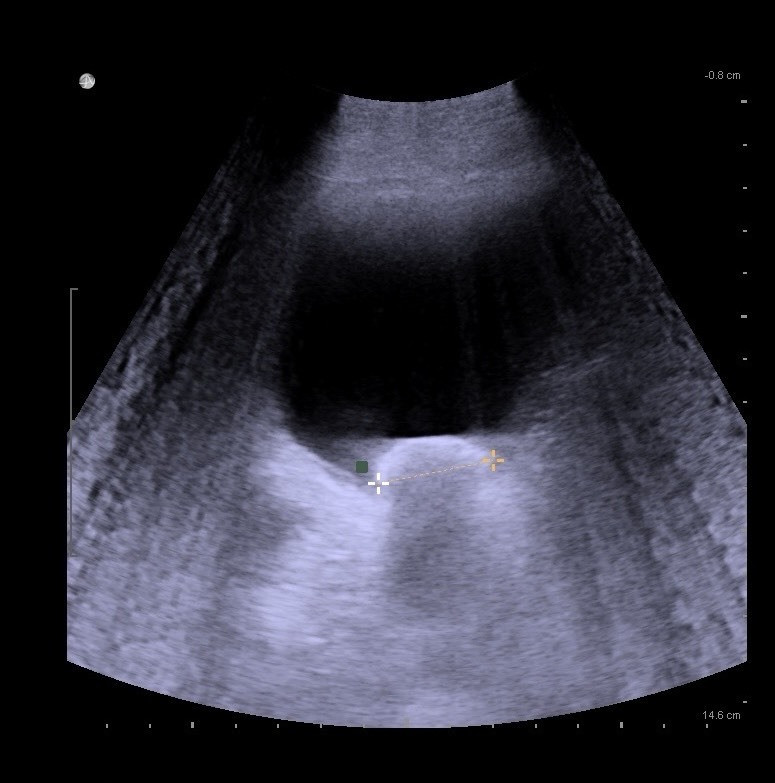

39歲壯男尿流中斷 超音波照出2.5公分大結石

〔記者王涵平/台南報導〕1名39歲壯年男子最近發現排尿時尿流會中斷,越來越常發生,前往部立新營醫院泌尿科求診,泌尿科主任陳建升在診間使用超音波掃描膀胱,赫然發現1顆2.5公分大的結石,安排病患住院接受內視鏡手術,手術順利將結石擊碎並取出。